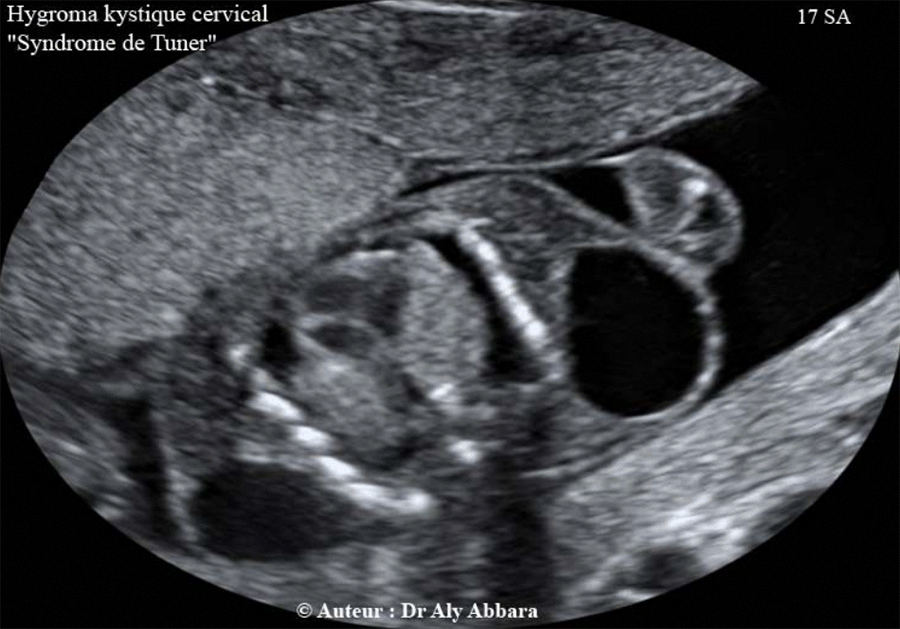

Hygroma Kystique Cervical Syndrome De Turner Cas Clinique Et Description De La Pathologie